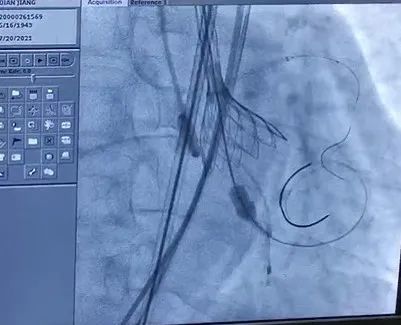

手术中

全麻后,成功穿刺右股动脉,通过穿刺点输送系统将瓣膜输送至病变的主动脉瓣处,经过严密地心电监护、心脏食道超声引导,手术团队在心室快速起搏下,使得收缩压降到 60 mmHg、脉压差小于 10 mmHg,此时释放人工生物瓣膜取代自身病变的瓣膜,食道超声检查无瓣周漏,人工瓣膜工作正常,手术完美结束。